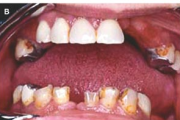

Sjögreni sündroomi võimalusele mõeldakse silmade ja suu kuivuse all kannatavatel patsientidel. Süsteemne haigus, mida iseloomustab kõigi eksokriinsete näärmete talitluse puudulikkus kroonilise põletikulise destruktsiooni tõttu.  Keratokonjunktiviit  Kserostoomia  Polüartriit Loe edasi »